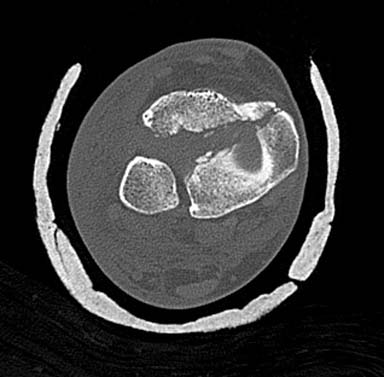

Сделал КТ контроль. Можно обойтись 3 винтами.В области эпифиза: 1 спонгиозный стягивающий винт провести снаружи кнутри, 2 стягивающий спонгиозный винт спереди назад и немного изнутри кнуаружи. На диафизе 1 кортикальный стягивающий винт. После операции 3 недели гипсовой иммобилизации, после чего рентген контроль и начинать постепенную поэтапную нагрузку на оперированную конечность. Сперва ходить 2 - 3 недели с нагрузкой "контакт с полом" + активное ЛФК с инструктором, затем еженедельно повышать нагрузку на 15% от массы тела, через 6 недель рентген контроль и ходить при помощи трости 1 месяц. Если поставить пластину, то срок консолидации будет такой же, но нагрузку можно давать раньше раньше. Джолдас, можете прокоментировать. Заранее благодарен.

С ответом немного задержался, хотел подобрать материал, но трудно найти идентичный случай. На всякий случай подобрал пару, надеюсь, поможет.

Первый случай, где перелом в результате падения с небольшой высоты, где мортиз рентген снимок показал отстутствие укорочения наружной

лодыжки и КТ срезы подсказали направления атаки. После такой фиксации нет надобности в гипсовой повязке, брейс и через две недели движения в

суставе без нагрузки.